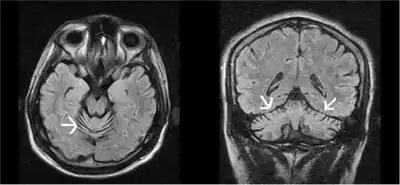

| MRI progressive ataxia due to alpha-tocopherol deficiency | |

- Rare disorders of fat metabolism – There is a rare genetic condition termed isolated vitamin E deficiency or 'ataxia with isolated with vitamin E deficiency', caused by mutations in the gene for the tocopherol transfer protein.[7] These individuals have an extremely poor capacity to absorb vitamin E and develop neurological complications that are reversed by high doses of vitamin E.